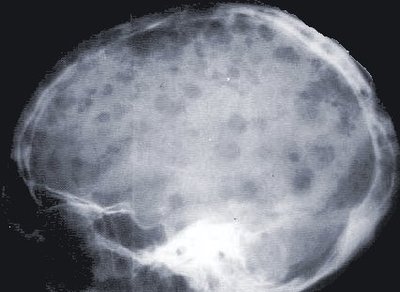

Séminaire d'information sur le Myélome

Appelée également maladie de Kahler, une maladie atteignant la moelle osseuse, cette réunion d'information s'adresse aux patients et leur famille. Elle est organisée par l'International Myeloma Foundation en collaboration avec des médecins spécialistes à 10h à la Maison de l'Amérique latine, 151 boulevard Saint-Germain.